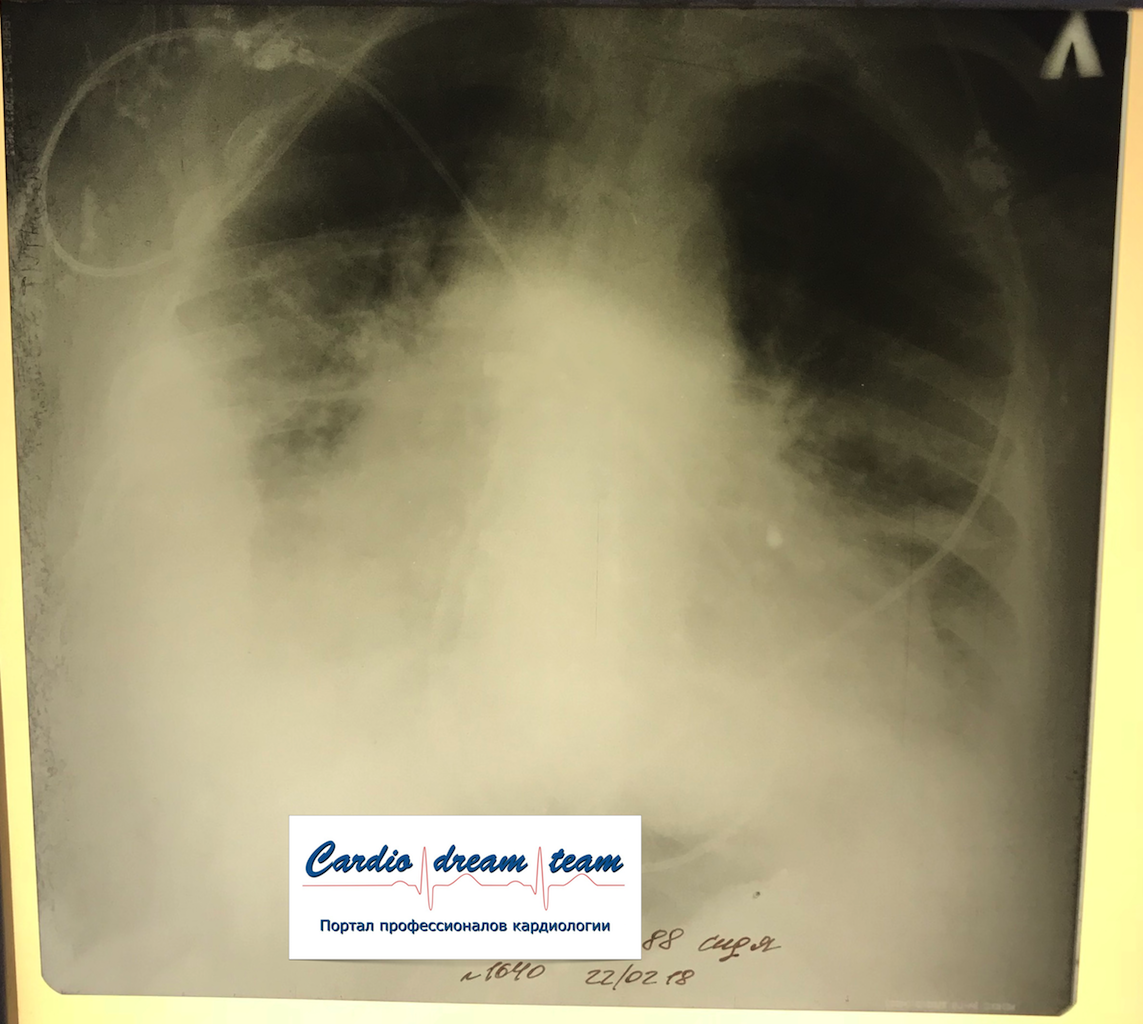

Гидроторакс. До и после пункции и лечения диуретиками.

Обсуждалось в Госпитале Ослабленных Сердец